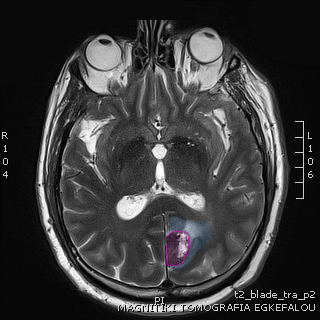

Όγκος εγκεφάλου με περιβάλλον οίδημα. |